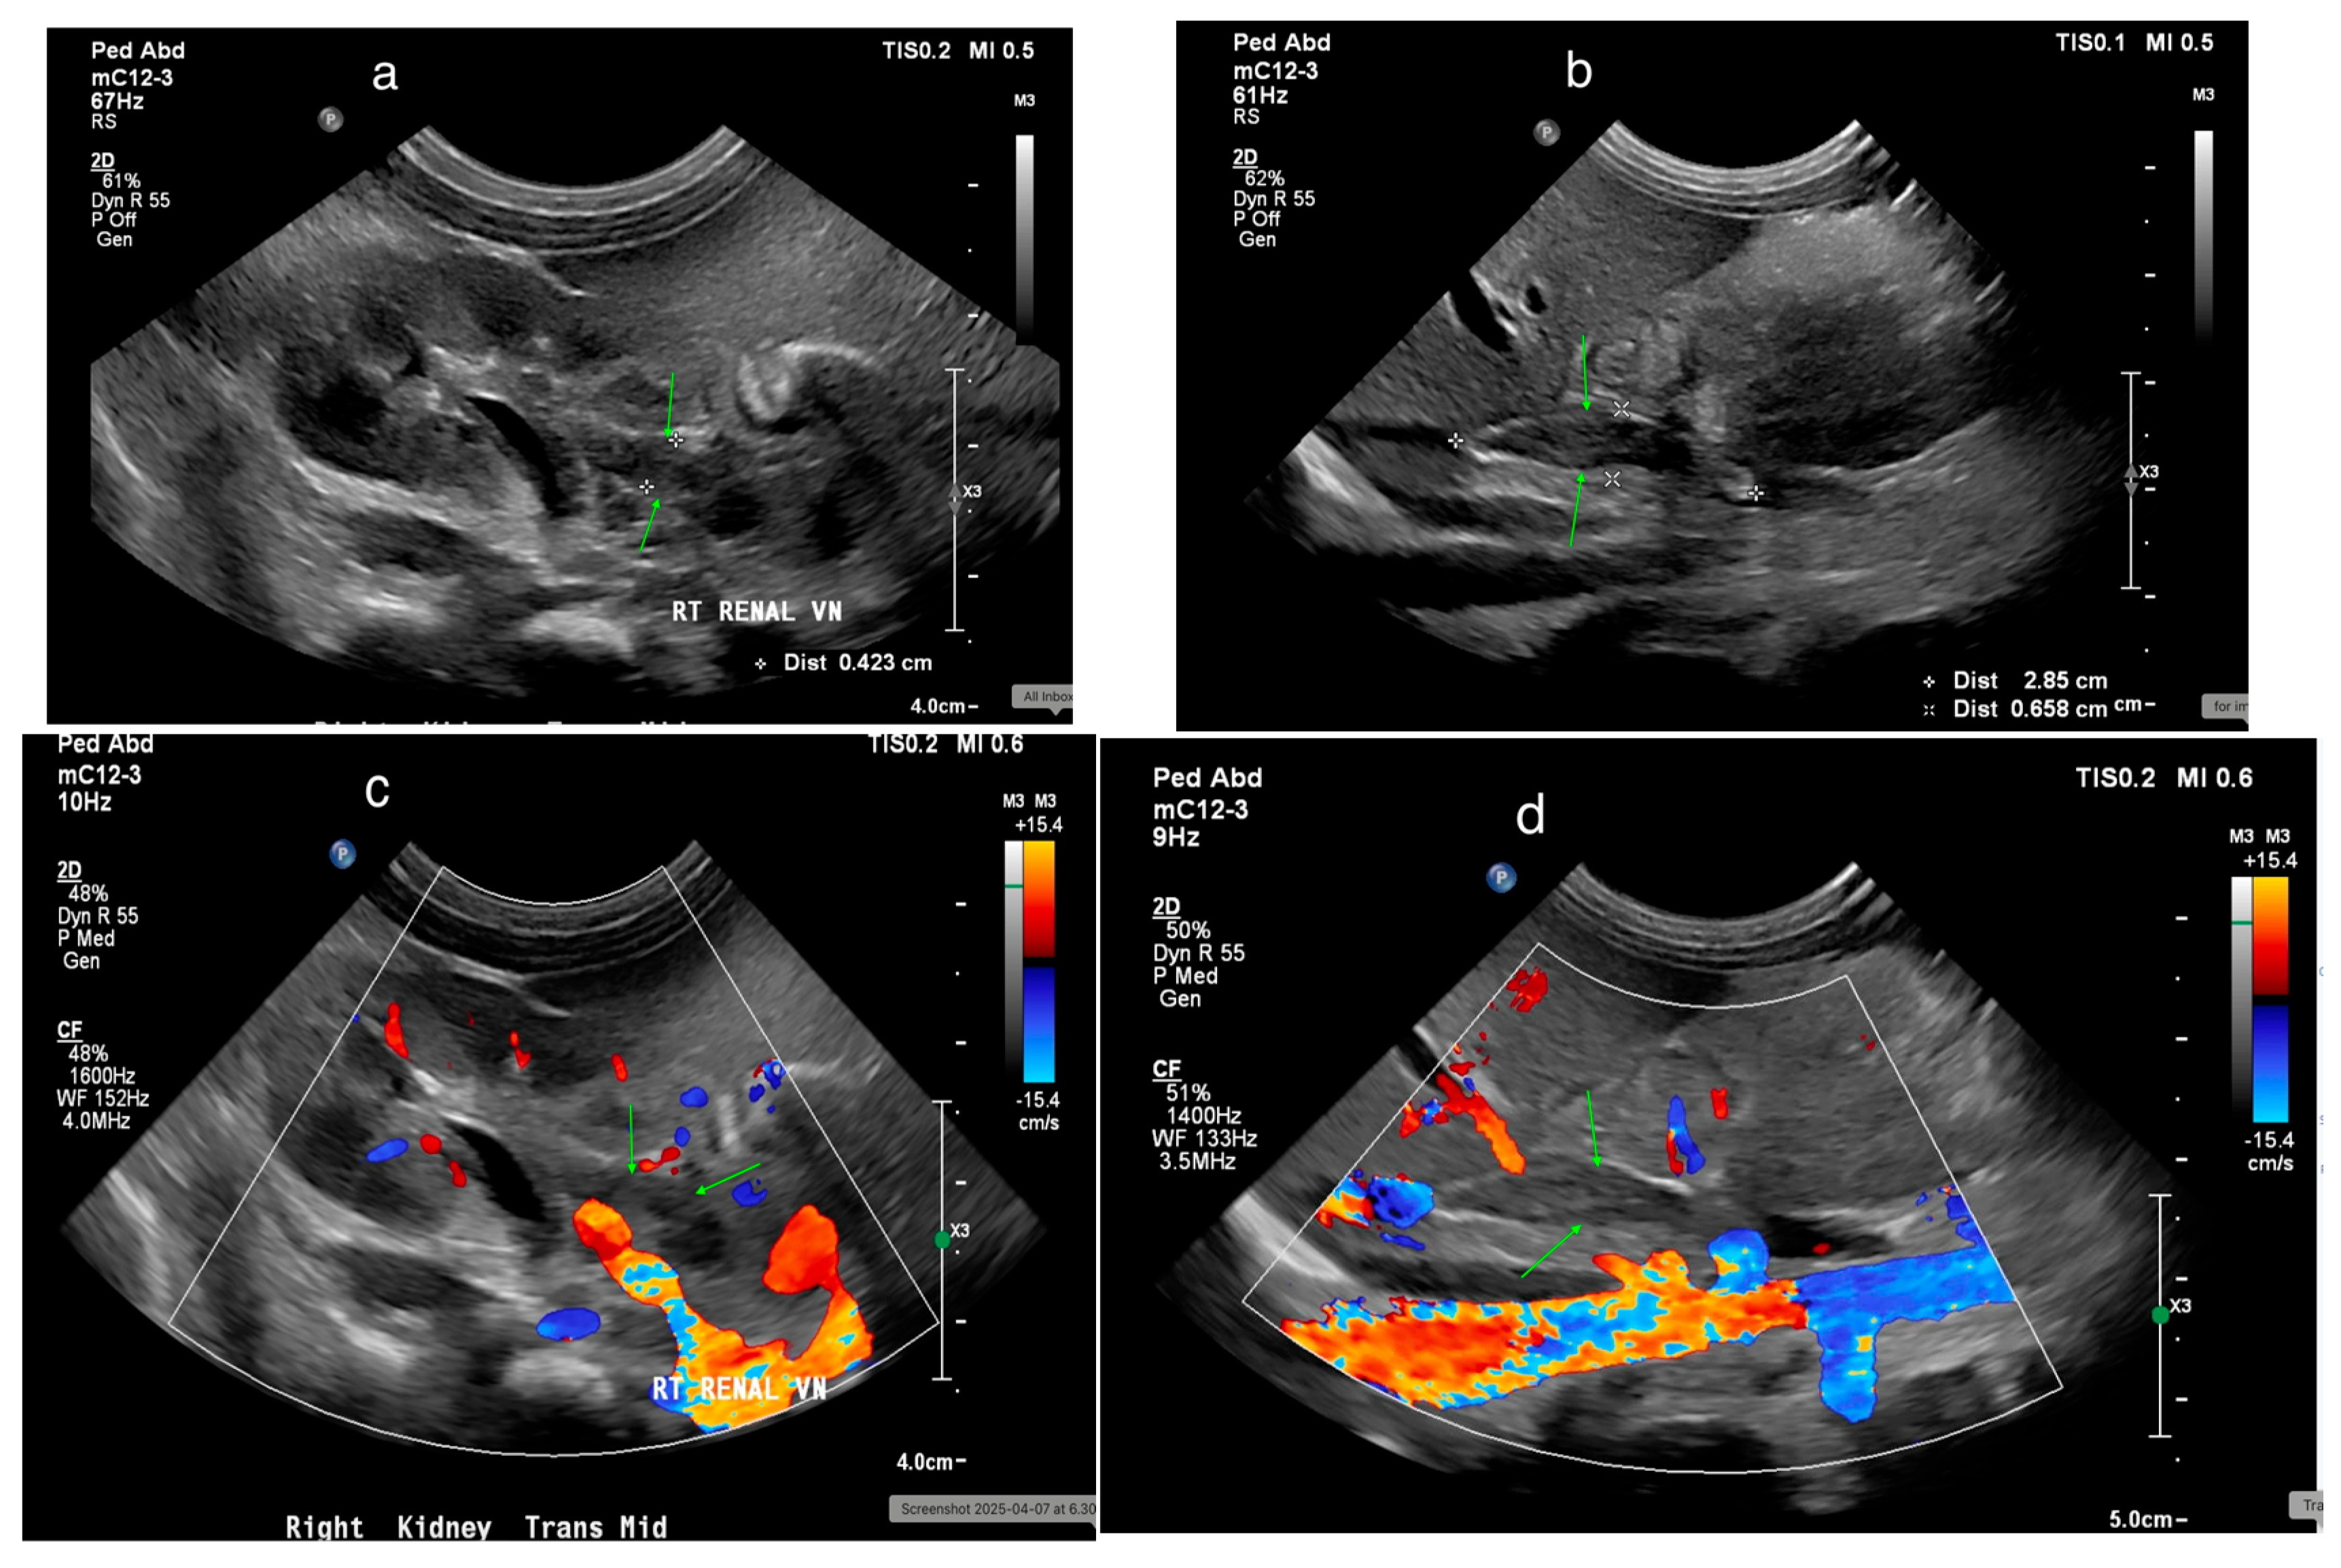

22.2. Renal Vein Thrombosis